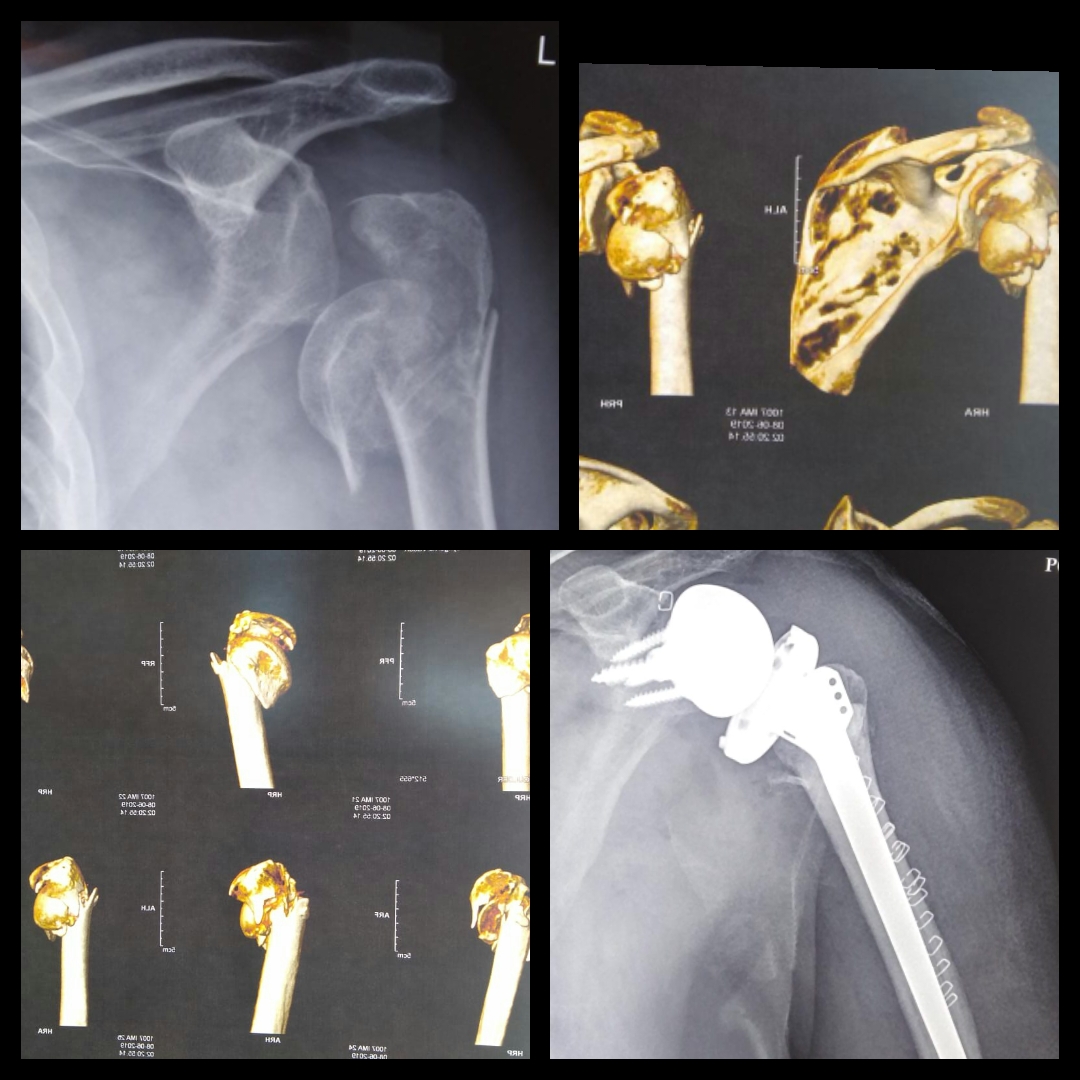

Dr. Amyn Rajani Performs Reverse Shoulder Arthroplasty for Proximal What Is A Partial Shoulder Replacement  In some people, the top of the arm bone needs to be replaced, but the socket is still in good shape. A shoulder replacement is surgery to replace your shoulder joint with an artificial one called a prosthesis. At surgery the ball at the top of the humerus is removed. It is commonly used to treat severe shoulder arthritis or. What Is A Partial Shoulder Replacement.